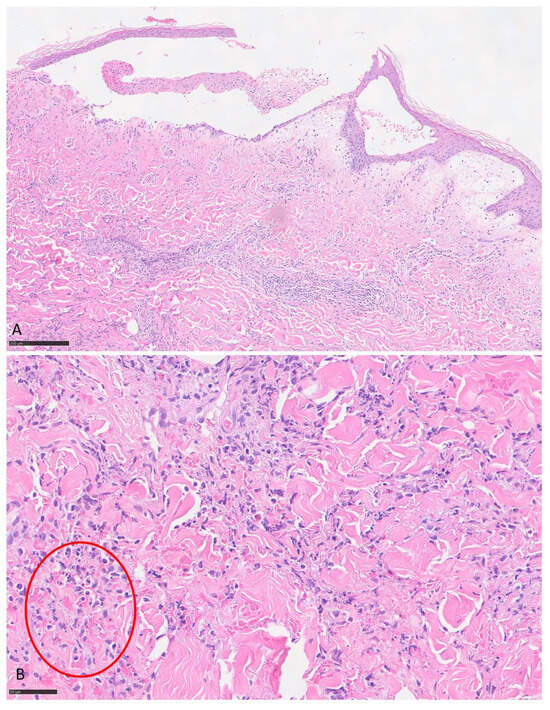

Steroid-Refractory Cholestatic Immune-Mediated Hepatitis Following Nivolumab Therapy in an Elderly Patient with Metastatic Melanoma: A Rare and Challenging Presentation

by Luis Posado-Dominguez, Jorge Feito-Perez, María Escribano-Iglesias, Miriam Bragado Pascual and Emilio Fonseca Sánchez

Curr. Oncol. 2025, 32(12), 663; https://doi.org/10.3390/curroncol32120663 - 27 Nov 2025

Immune checkpoint inhibitors (ICIs) have revolutionized the treatment of advanced malignancies, but they may cause a wide range of immune-related adverse events (irAEs). Hepatic toxicity occurs in approximately 1–6% of patients treated with nivolumab and usually presents with a hepatocellular pattern responsive to [...] Read more.

Immune checkpoint inhibitors (ICIs) have revolutionized the treatment of advanced malignancies, but they may cause a wide range of immune-related adverse events (irAEs). Hepatic toxicity occurs in approximately 1–6% of patients treated with nivolumab and usually presents with a hepatocellular pattern responsive to corticosteroids. The cholestatic-predominant immune-mediated hepatitis seems to respond poorly to immunosuppression. We describe an 87-year-old man with metastatic melanoma treated with nivolumab who developed steroid-refractory, cholestatic-predominant immune-mediated hepatitis after 18 cycles of therapy. Laboratory tests revealed a mixed but predominantly cholestatic pattern (ALT 585 U/L, GGT 2261 U/L, total bilirubin 2.0 mg/dL). Imaging excluded biliary obstruction or hepatic metastases. Liver biopsy showed acute lobular hepatitis with intracanalicular cholestasis and mild bile duct injury, consistent with immune-mediated, drug-induced injury (Ishak score 5). Mycophenolate mofetil produced only partial biochemical improvement. The patient died one month later from influenza A pneumonia in the context of combined immunosuppressive therapy. This case illustrates a cholestatic-predominant phenotype of nivolumab-induced hepatitis, characterized by poor corticosteroid response and incomplete recovery despite second-line immunosuppression. Recognition of this entity is essential, as early introduction of agents such as mycophenolate may improve outcomes. In elderly and frail patients, however, the risks of intensified immunosuppression must be carefully balanced against infection risk, highlighting the need for individualized management and vigilant monitoring. Full article

Show Figures

Figure 1